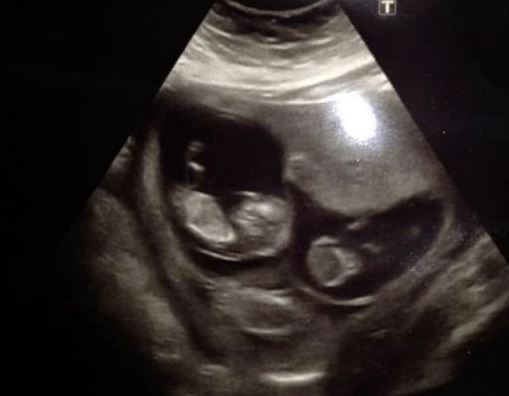

Η Σάρα Γουόρντ που μέχρι πέρσι ανησυχούσε ότι δεν θα γίνει ποτέ μητέρα, πρόκειται σύντομα να γίνει πολύτεκνη.  Είχε κάνει αρκετές προσπάθειες με τον σύντροφό της να γίνουν γονείς αλλά δεν τα κατάφερναν μέχρι πριν από 16 μήνες που έμεινε έγκυος στον Φρέντι. Τώρα ο Φρέντι είναι ήδη επτά μηνών αλλά κι εκείνη είναι επτά μηνών έγκυος αφού μόλις γέννησε έμεινε ξανά έγκυος! Κι αυτή τη φορά τα μωρά είναι τρία!

Οπότε τον Μάρτιο που θα γεννηθούν τα τρία αδερφάκια του, ο Φρέντι θα είναι εννέα μηνών.

Η 28χρονη Σάρα και ο σύντροφός της μένουν σε σπίτι με μία μόνο κρεβατοκάμαρα αλλά σύντομα θα χρειαστεί να μετακομίσουν: «Το να μείνω έγκυος αμέσως μετά την πρώτη μου γέννα ήταν μεγάλο σοκ για μένα. Μόλις δε έμαθα ότι είναι τρίδυμα σχεδόν έπεσα κάτω! Θα είναι τρελό να έχουμε τέσσερα παιδιά, όλα μωρά, αλλά ανυπομονώ τόσο να τα κρατήσω στην αγκαλιά μου. Νιώθω ευλογημένη!».